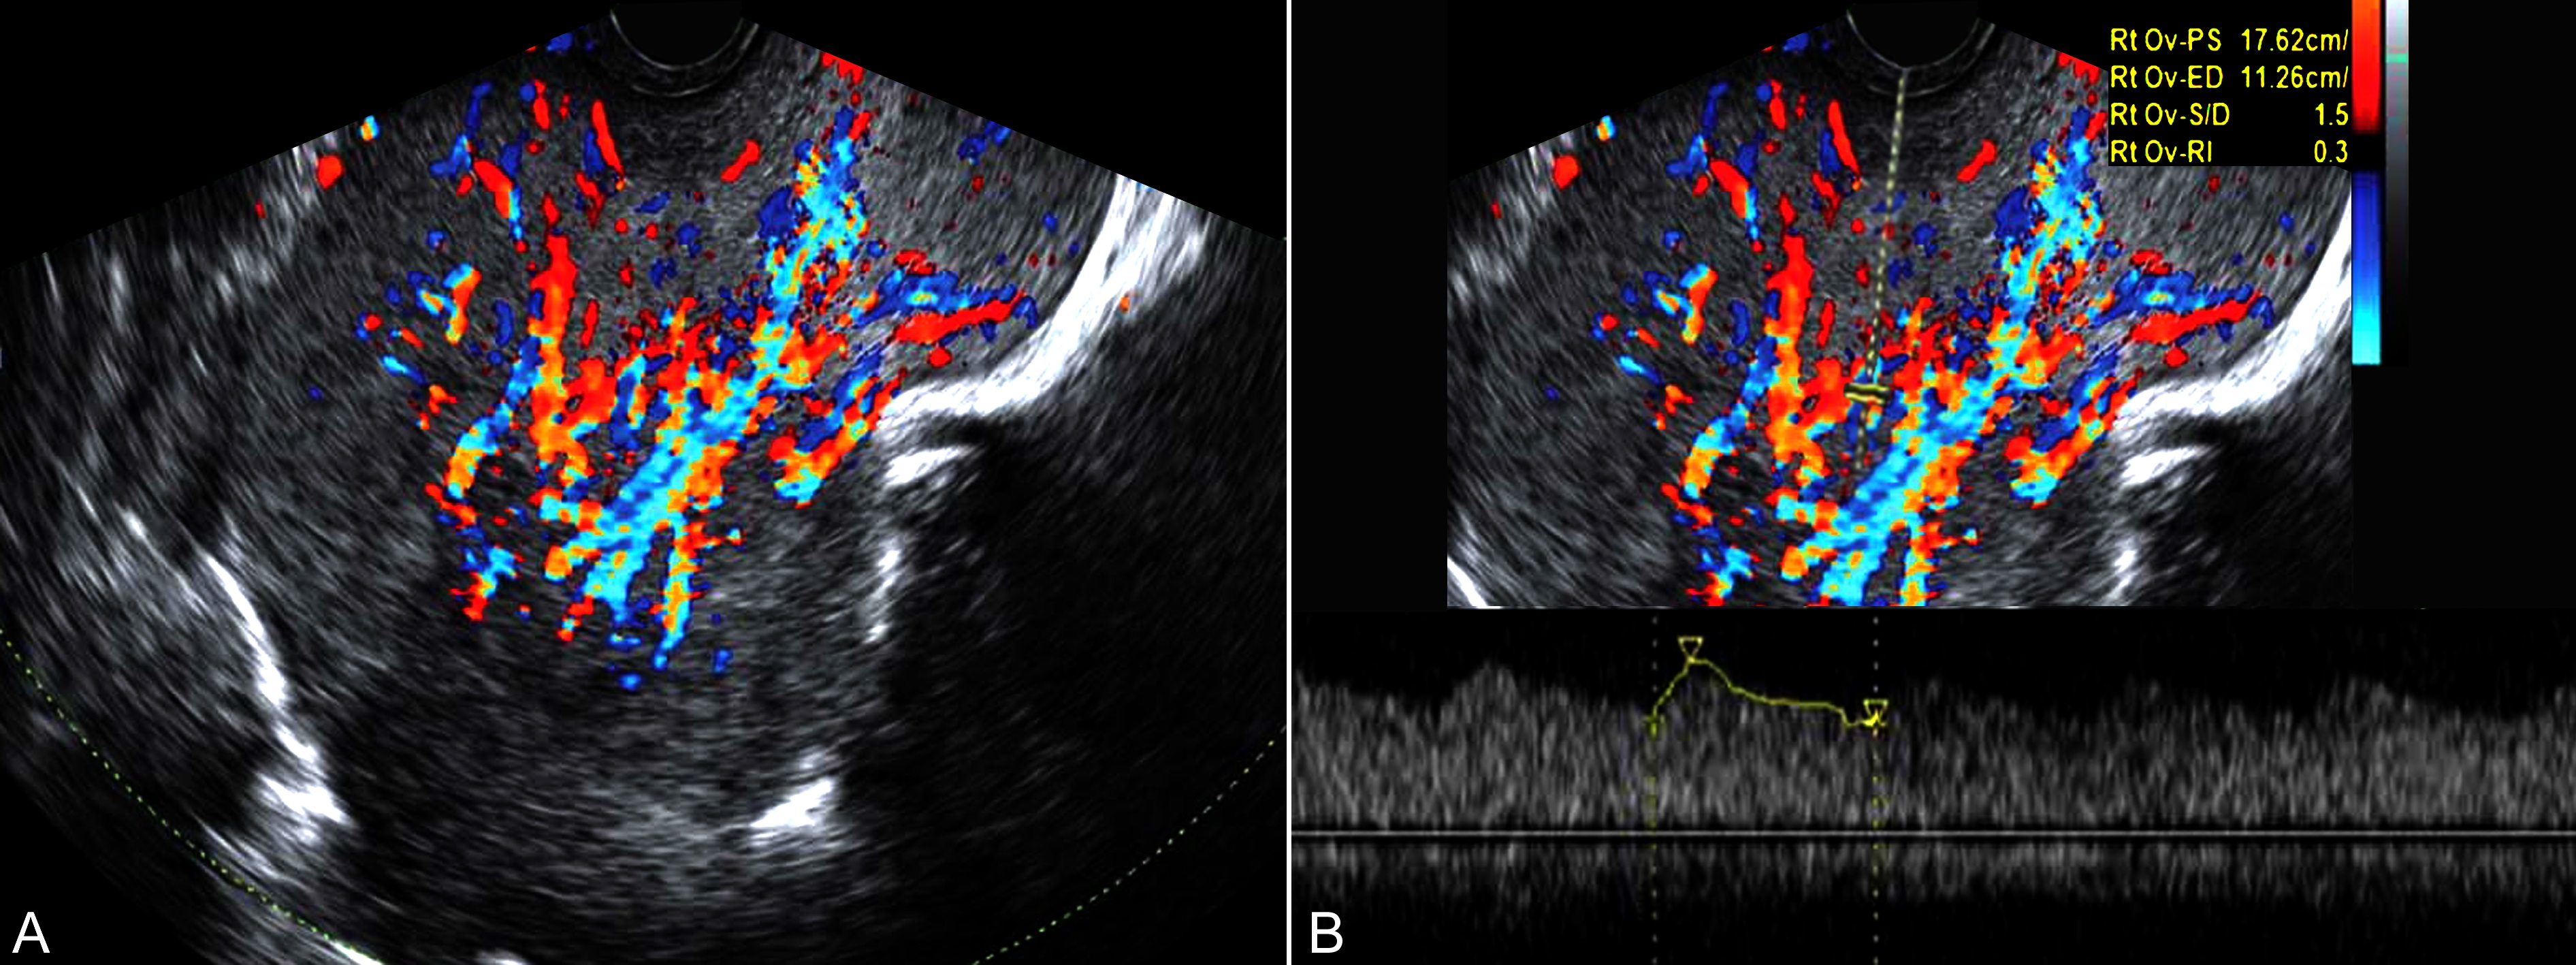

超声显像检查可在妊娠的各个时期发现,声像图表现为增大的子宫一侧或两侧、或于子宫后方局限性回声,肿瘤较小时显示形态规则,多数瘤体发现时已显示不规则,边缘不整齐、不清晰(图2),以原发病灶的性质不同内部回声的性质有所差异,多显示为较低的不均质回声,分布不均匀,CDFI检查内部可见点状或细小的血流显示,部分血流显示丰富(图3)。腹腔内多可显示不等的腹水。

图3库勃氏瘤血流显示:瘤体显示为不均匀型实质性回声,内部血流丰富,为低速、低阻力型